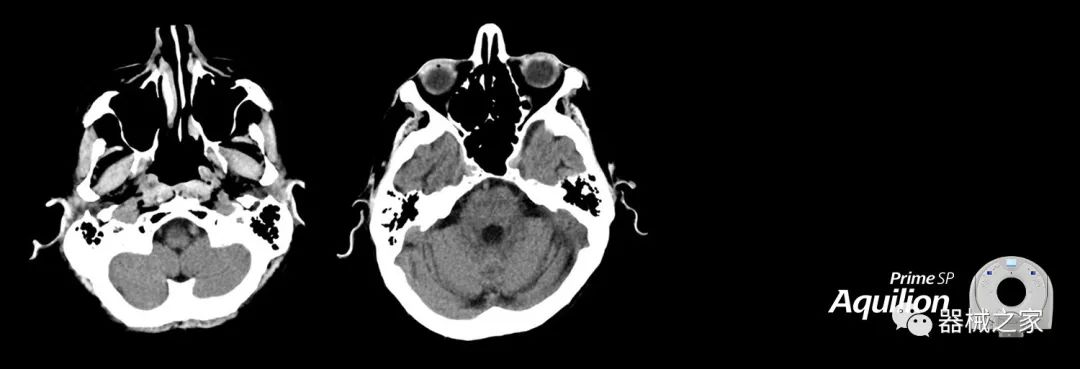

Aquilion Prime SP使設(shè)施能夠處理具有挑戰(zhàn)性的案例,同時(shí)為員工提供快速,靈活和高效的解決方案。

佳能醫(yī)療的Aquilion Lightning 80掃描儀還以緊湊,經(jīng)濟(jì)的包裝提供高質(zhì)量的成像。Aquilion Lightning 80旨在可靠,高效地運(yùn)行,在繁忙的環(huán)境中生成高質(zhì)量的圖像。

兩個(gè)CT系統(tǒng)均采用0.5 mm x 80排PUREViSION探測(cè)器技術(shù)(可配置并從80-160現(xiàn)場(chǎng)升級(jí)),78 cm孔徑,50 cm視野,AIDR(自適應(yīng)迭代劑量減少)3-D和SEMAR(單個(gè))能量金屬神器減少)技術(shù)。